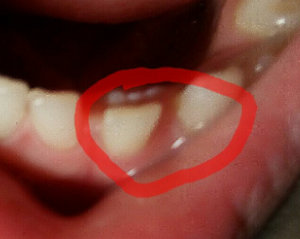

Дочке 7 лет, возраст, когда молочные зубки выпадают. Начал шататься верхний второй зуб слева. Сегодня заметила, что рядом режется зуб, но только совсем не там, где я его ожидала.

Подскажите, можно ли будет как-то исправить ситуацию? Он как-то совсем не там, где нужно растет. Причем, жалоб от нее не поступало, ничего не болело. Честно, я в панике, хочется, чтобы у девочки были красивые, ровные зубки. Что делать?